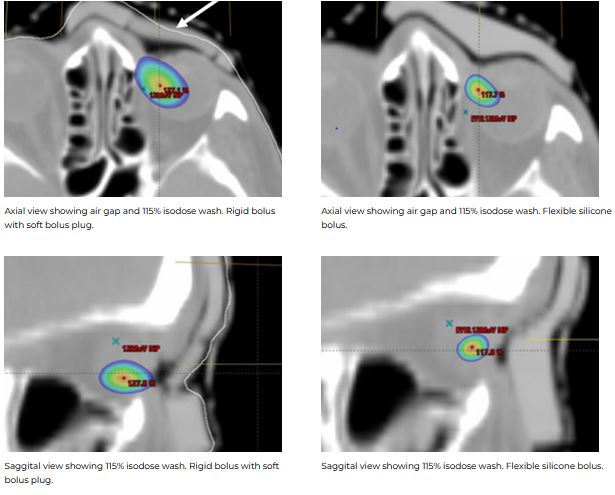

Both showed good conformity to the body surface. The air gap volume over the inner canthus was 1.27 cc for the 3D rigid bolus, corresponding to the location of the soft bolus plug. The measured air gap volume under the silicone bolus in this same region was 0.24 cc.

Both demonstrated good material homogeneity between 120-150 HU and 160-190 HU for the rigid and silicone boluses. PTV Dmax for the rigid bolus was 125.5% versus 116.6% for the silicone bolus. Dmax for OARs was comparable except for the left eye, which had a maximum difference of a reduction of 14% when using the silicone bolus.

While both boluses showed a close fit to the skin surface, the generic bolus plug introduced an air gap under the rigid bolus resulting in an overdose to the distal PTV and a higher dose to the underlying left eye. The soft and malleable nature of the silicone bolus allowed it to adjust to the contour of the bolus plug without modification.